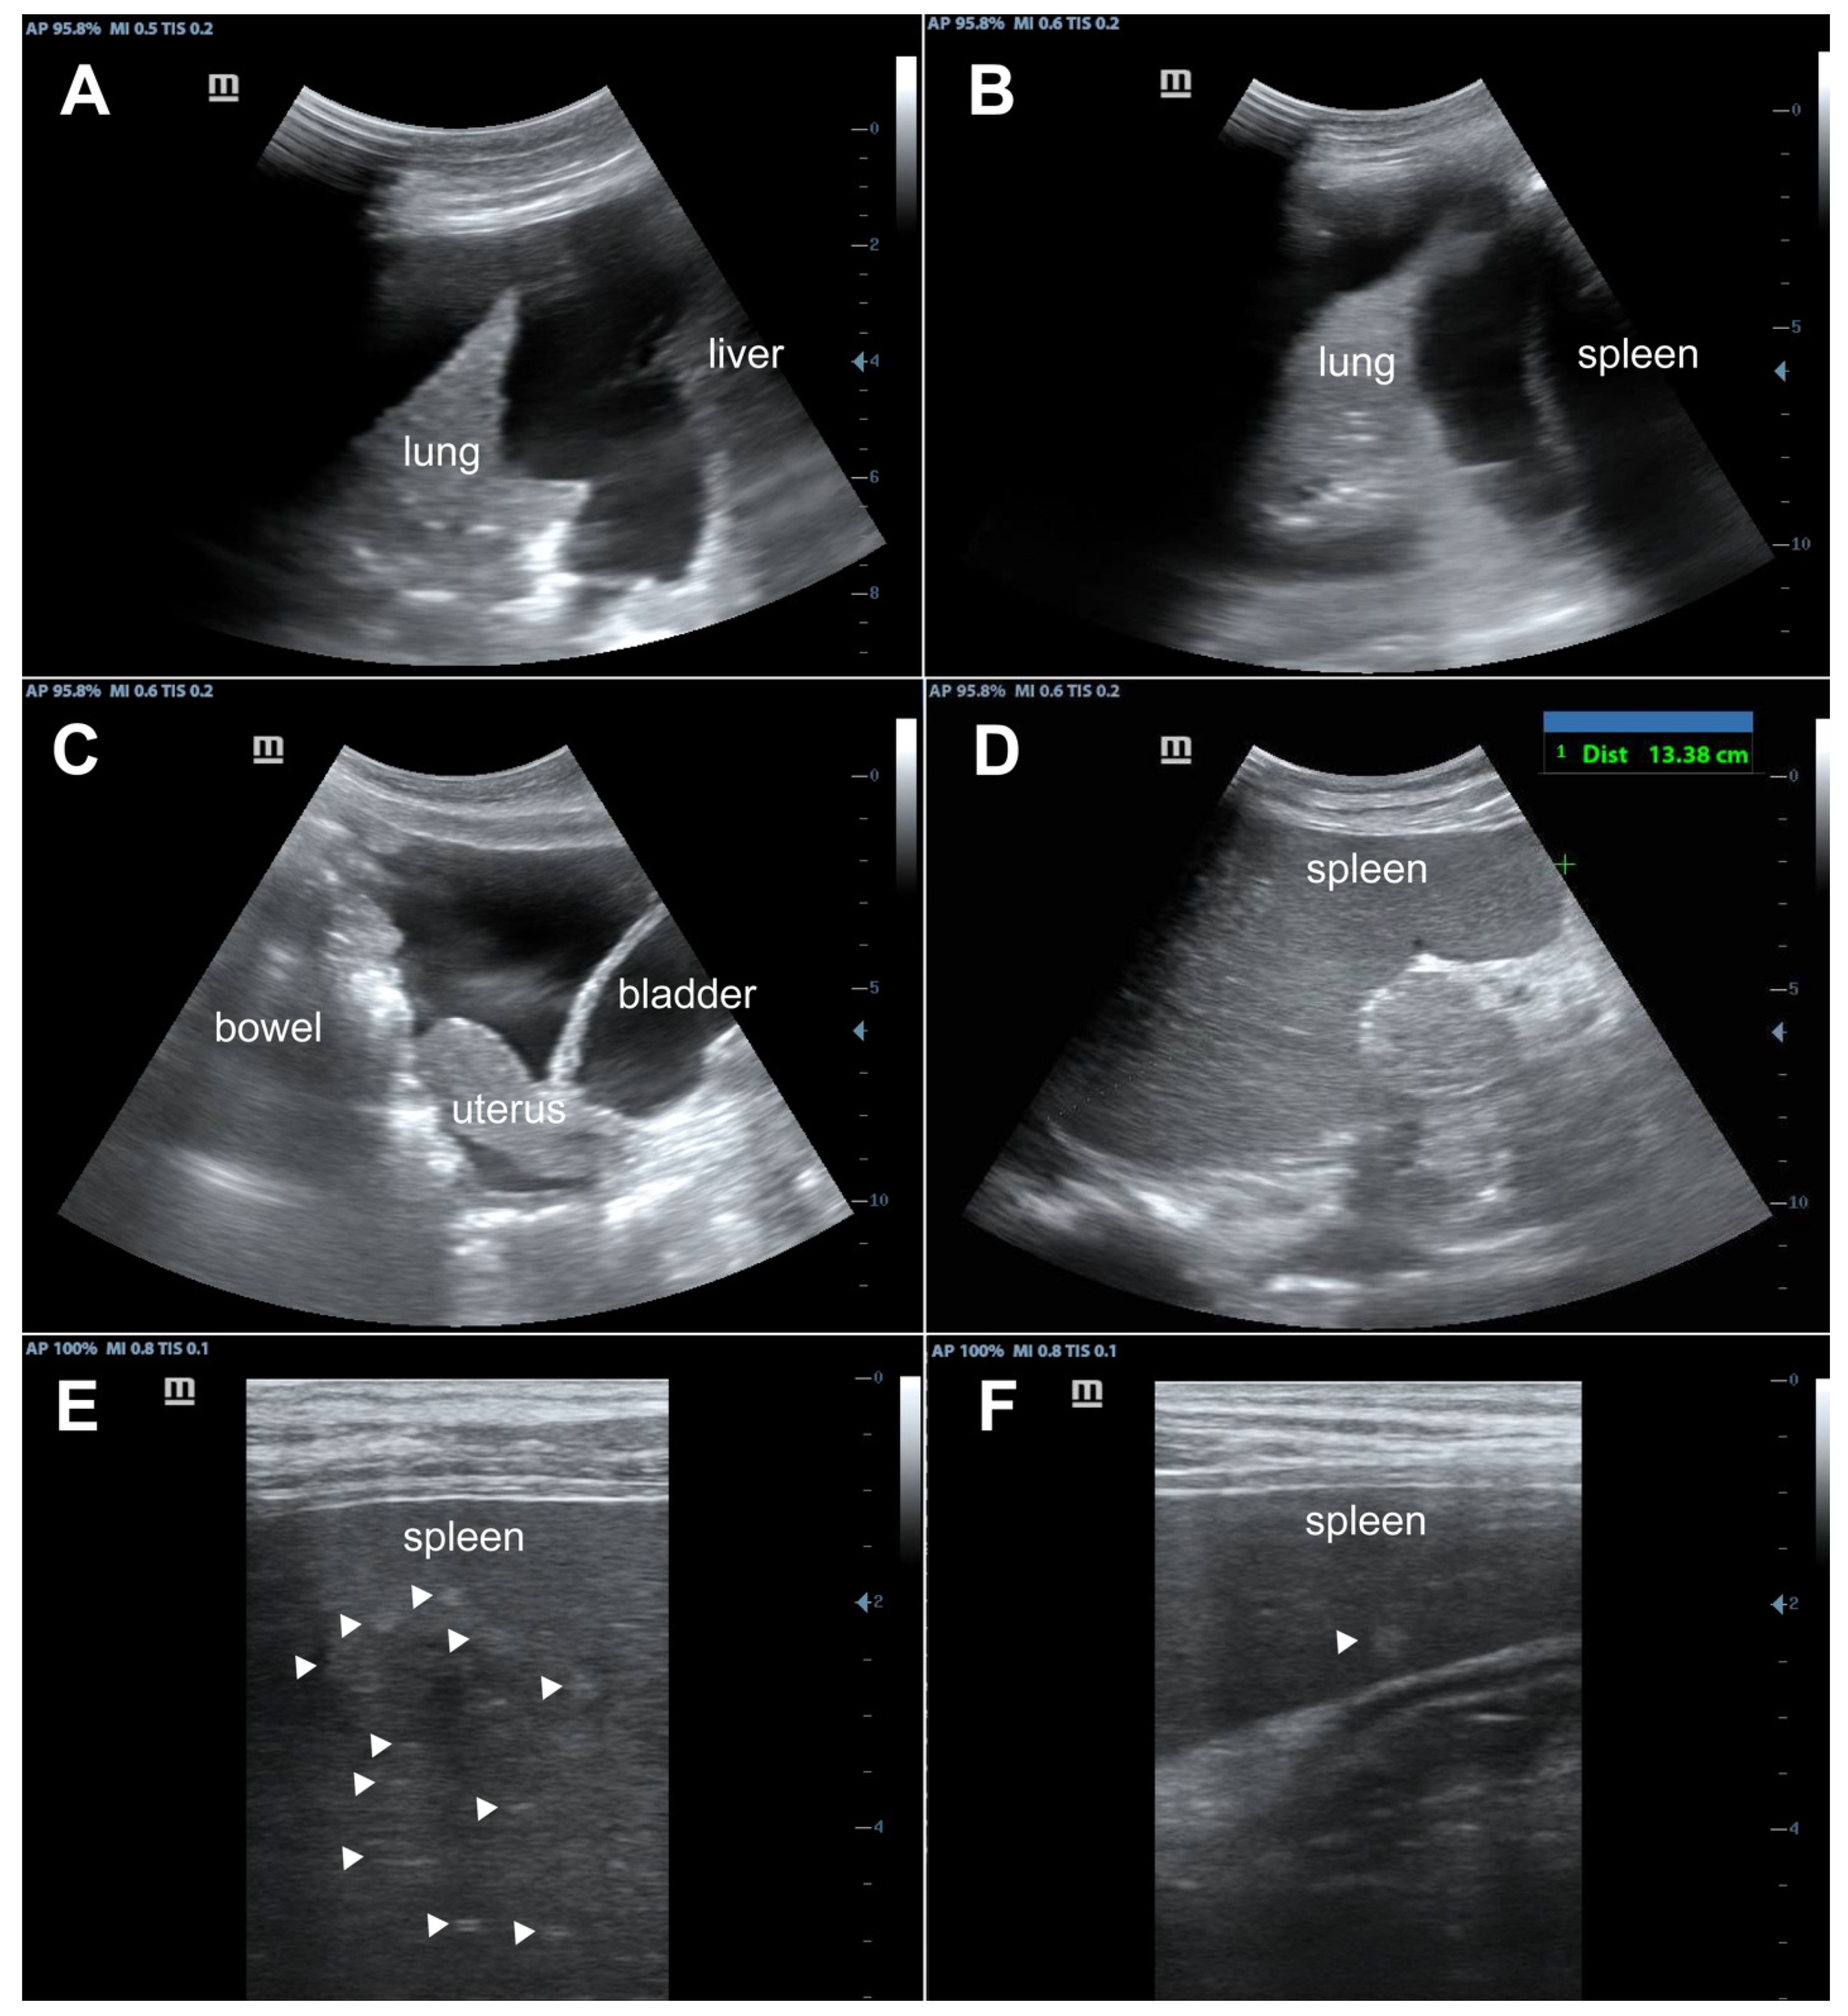

| Day 2 | Ultrasound revealed bilateral pleural effusions, pelvic free fluid, and hyperechoic splenic lesions consistent with disseminated KS. Right thoracentesis removed 1300 mL blood-stained fluid. Received first cycle of IV paclitaxel 100 mg/m2, IV dexamethasone 12 mg, third dose of ceftriaxone 2 g. |

- Huson, M.A.M.; Kumwenda, T.; Gumulira, J.; Rambiki, E.; Wallrauch, C.; Heller, T. Ultrasound findings in Kaposi sarcoma patients: Overlapping sonographic features with disseminated tuberculosis. Ultrasound J. 2023, 15, 27. [Google Scholar] [CrossRef] [PubMed]